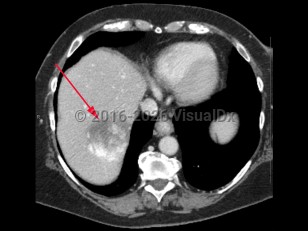

Hepatic hemangioma

Most hepatic hemangiomas are asymptomatic and are incidental findings on abdominal imaging. Larger lesions are more likely to cause symptoms, including abdominal pain (especially in the upper right quadrant), nausea, and anorexia. Women are 3 times as likely to develop hemangiomas and are more likely to experience symptoms. The etiology of hepatic hemangiomas is unclear, but hormonal influence over tumor enlargement may explain the higher incidence of symptomatic lesions in women. Lesions may grow during pregnancy and in the setting of oral contraceptive therapy. Surgical resection may be necessary for patients experiencing pain.